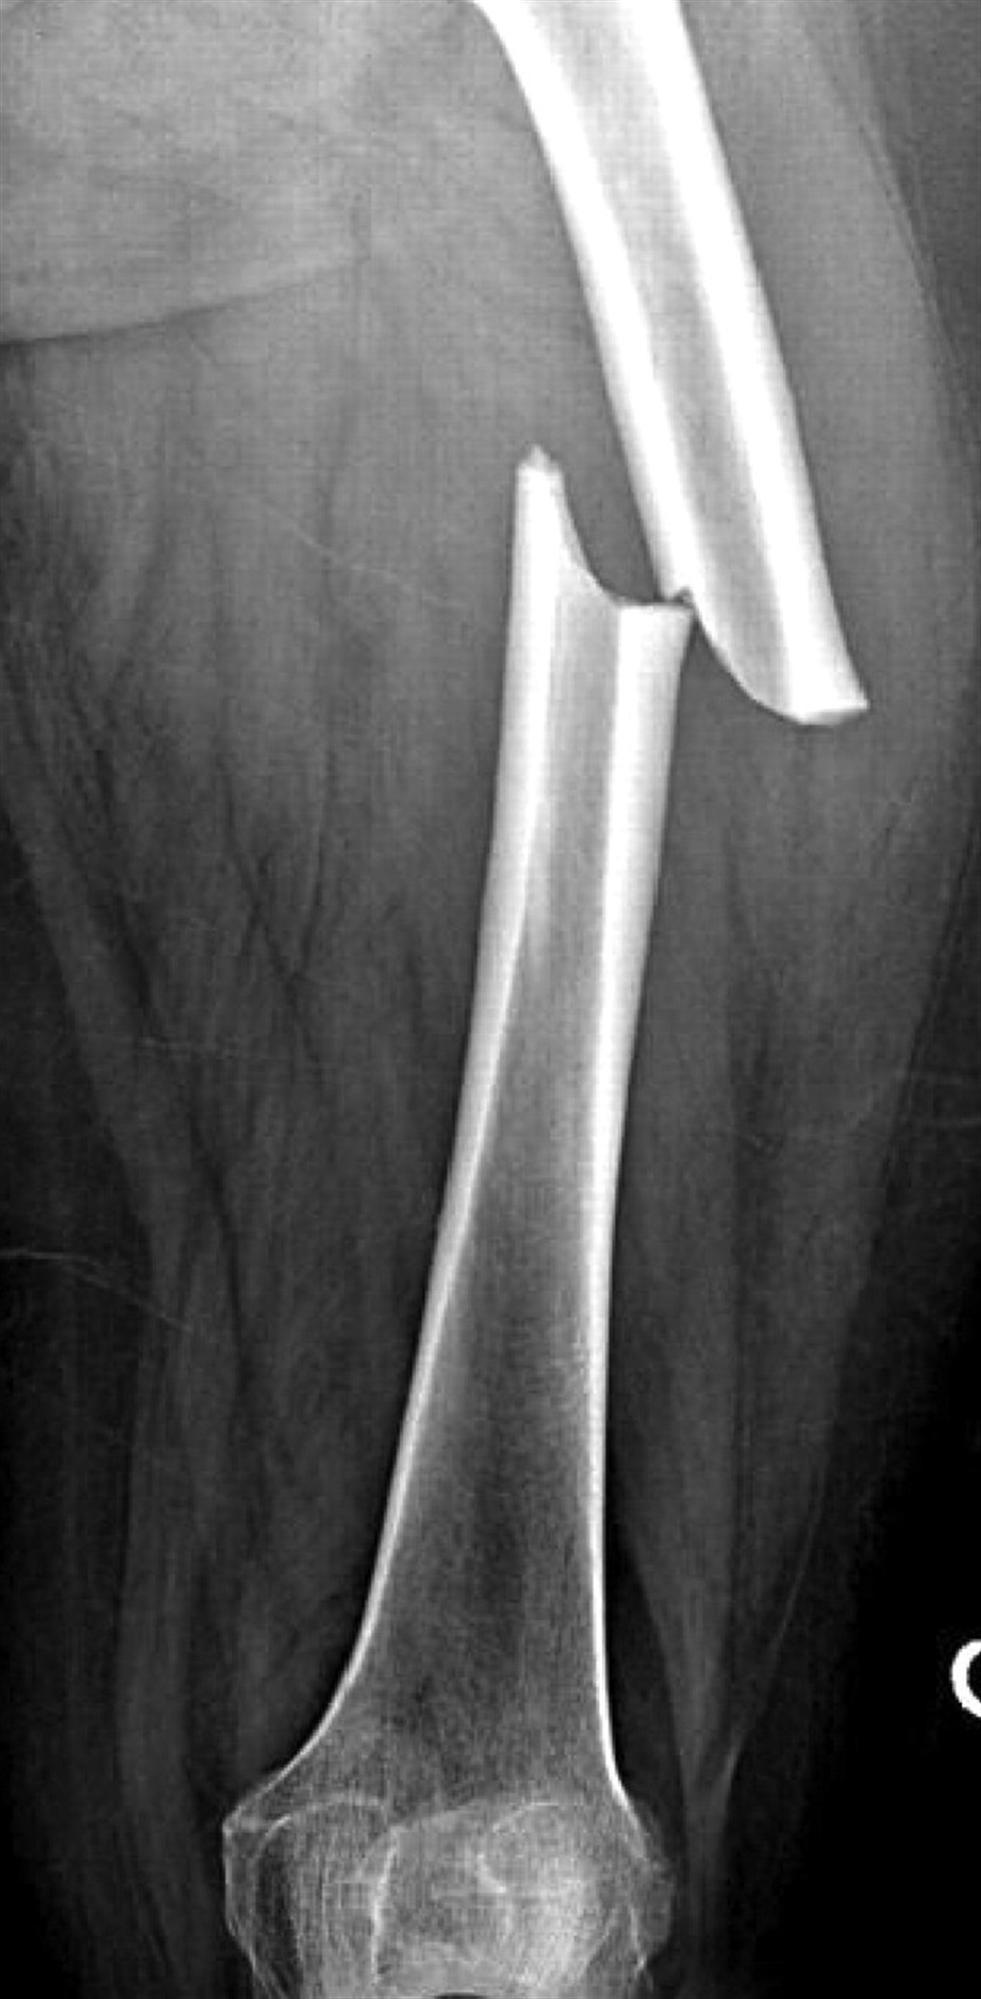

What is meant by a distal femoral fracture?

Fracture between the distal metaphyseal-diaphyseal junction of femur to the articular surface of femoral condyles